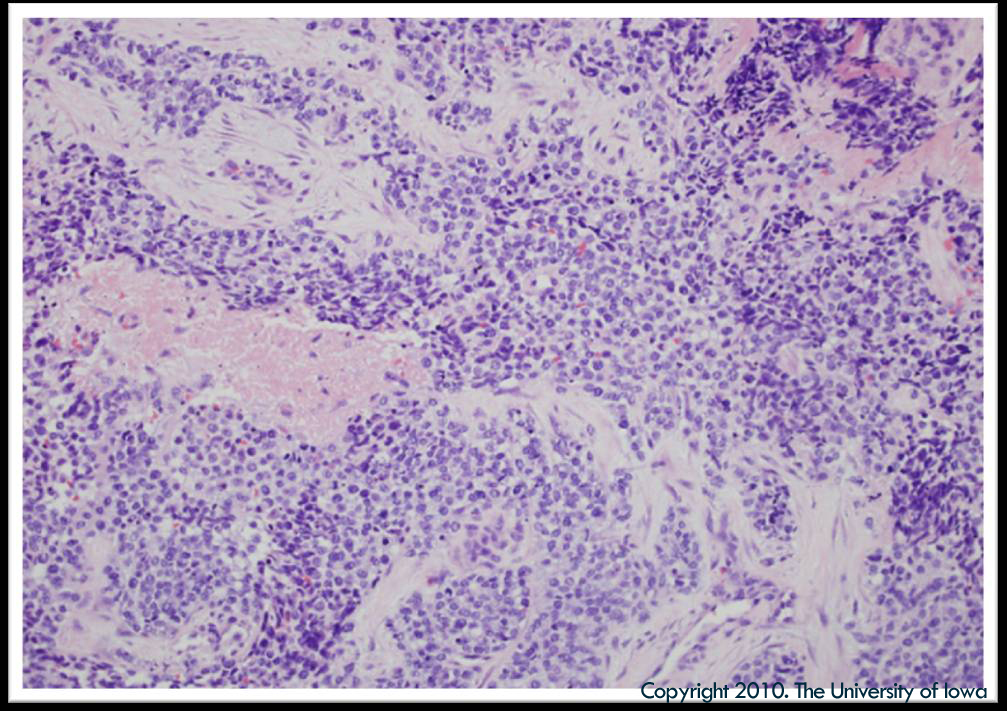

Figure 6a: Histopathology showing small, round, blue cells with spindle cells that have features of skeletal muscle in various stages of embryogenesis revealing the diagnosis of rhabdomyosarcoma (RMS) (click on image for higher resolution image)

Figure 6b: Higher magnification of Figure 6a (click on image for higher resolution image)

The presenting symptoms of ocular RMS include: proptosis (80-100%), globe displacement (80%), blepharoptosis (30-50%), conjunctival and eyelid swelling (60%), palpable mass (25%), and pain (10%) (Shields and Shields 2003). Although trauma does not cause RMS, it is not unusual for a patient to present with a history of recent injury preceding the ocular or orbital findings. RMS must be considered in all patients, particularly children, who present with proptosis. Decreased visual acuity tends to be a late clinical finding, and consequently, indicative of advanced disease. Initial work-up includes imaging—CT, MRI, or both—which subsequently guides surgical planning for incisional versus excisional biopsy. Final diagnosis is based on histopathology. Fine needle aspiration does not produce enough tissue to make an adequate histopathologic diagnosis. There are four histopathologic subtypes of RMS: embryonal, alveolar, pleomorphic, and boytroid (Holds et al. 2010). Embryonal RMS is associated with a 94% survival rate and accounts for 80% of orbital RMS. Contrariwise, alveolar RMS is the most malignant subtype (with a 10% 10-year survival rate) and comprises 9% of orbital RMS. Pleomorphic RMS is the least common and the most differentiated form; it is most commonly found in adults. Boytroid RMS is a rare variant of embryonal RMS and is not found as a primary tumor of the orbit (Holds et al. 2010). Histopathologic diagnosis of RMS requires immediate involvement of a pediatric hematologist/oncologist to further guide evaluation and management. A complete work-up includes: labs, bone marrow biopsy, bone scan, PET scan, CT of the chest/abdomen/pelvis, and cerebral spinal fluid analysis with cytology when applicable (Hayes-Jordan and Andrassy 2009).